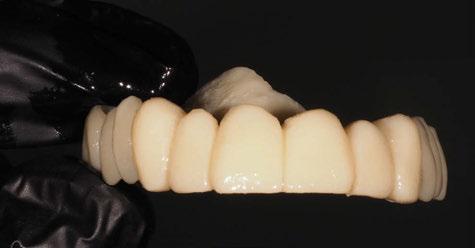

5. Fase protésica definitiva

A los 4 meses, se retiró la prótesis provisional, verificando la